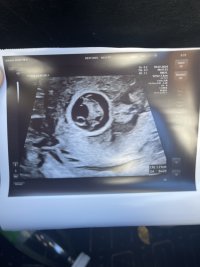

Hun sa og at det så veldig ut som en jente basert på hvor tydelig det viste, men selvfølgelig er det tidlig enda. Hun pleide normalt sett ikke uttale seg så tidlig men her syns hun det var greit å se. Vi har en av hver så begge deler er like kjekt, men hva tror dere basert på NUB?Jeg ville også sagt jente!Privat ul i dag før ferien med fosterdiagnostikk 11+4. Ble målt til rett under 5 cm, veldig fine mål på nakkefold, og ellers tipp topp anatomi og hjerterytme. Alt var som det skulleHun sa og at det så veldig ut som en jente basert på hvor tydelig det viste, men selvfølgelig er det tidlig enda. Hun pleide normalt sett ikke uttale seg så tidlig men her syns hun det var greit å se. Vi har en av hver så begge deler er like kjekt, men hva tror dere basert på NUB?

Var dette ordinær tidlig ultralyd?11+2![]()